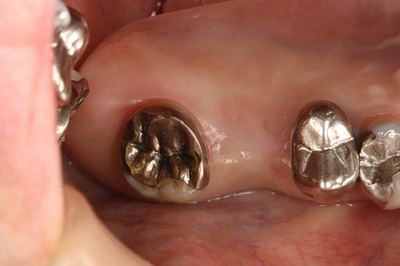

この部分にインプラントを植立します。

CTデータと重ね合わせて予定位置・方向に金属棒を植えます。

上下の歯の位置関係も確認します。